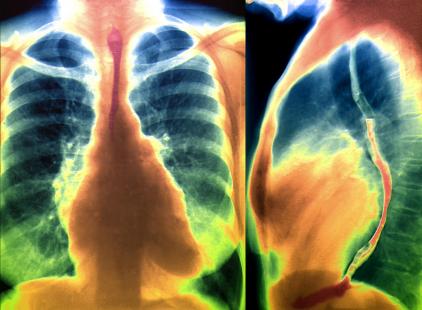

Le système MitraClip fait appel à une technique qui consiste à reproduire par voie percutanée l’intervention chirurgicale d’Alfieri. Son objectif est de transformer un orifice mitral incompétent en un double orifice compétent grâce à la réunion et la suture de la partie médiane du bord libre des 2 feuillets mitraux. Le dispositif utilisé est un clip fabriqué en alliage métallique, recouvert d'un tissu en polyester couramment utilisé pour les implants cardiovasculaires. Il est constitué de 2 bras et de 2 grippers entre lesquels sont agrippés et maintenus les bords libres des 2 feuillets mitraux opposés.